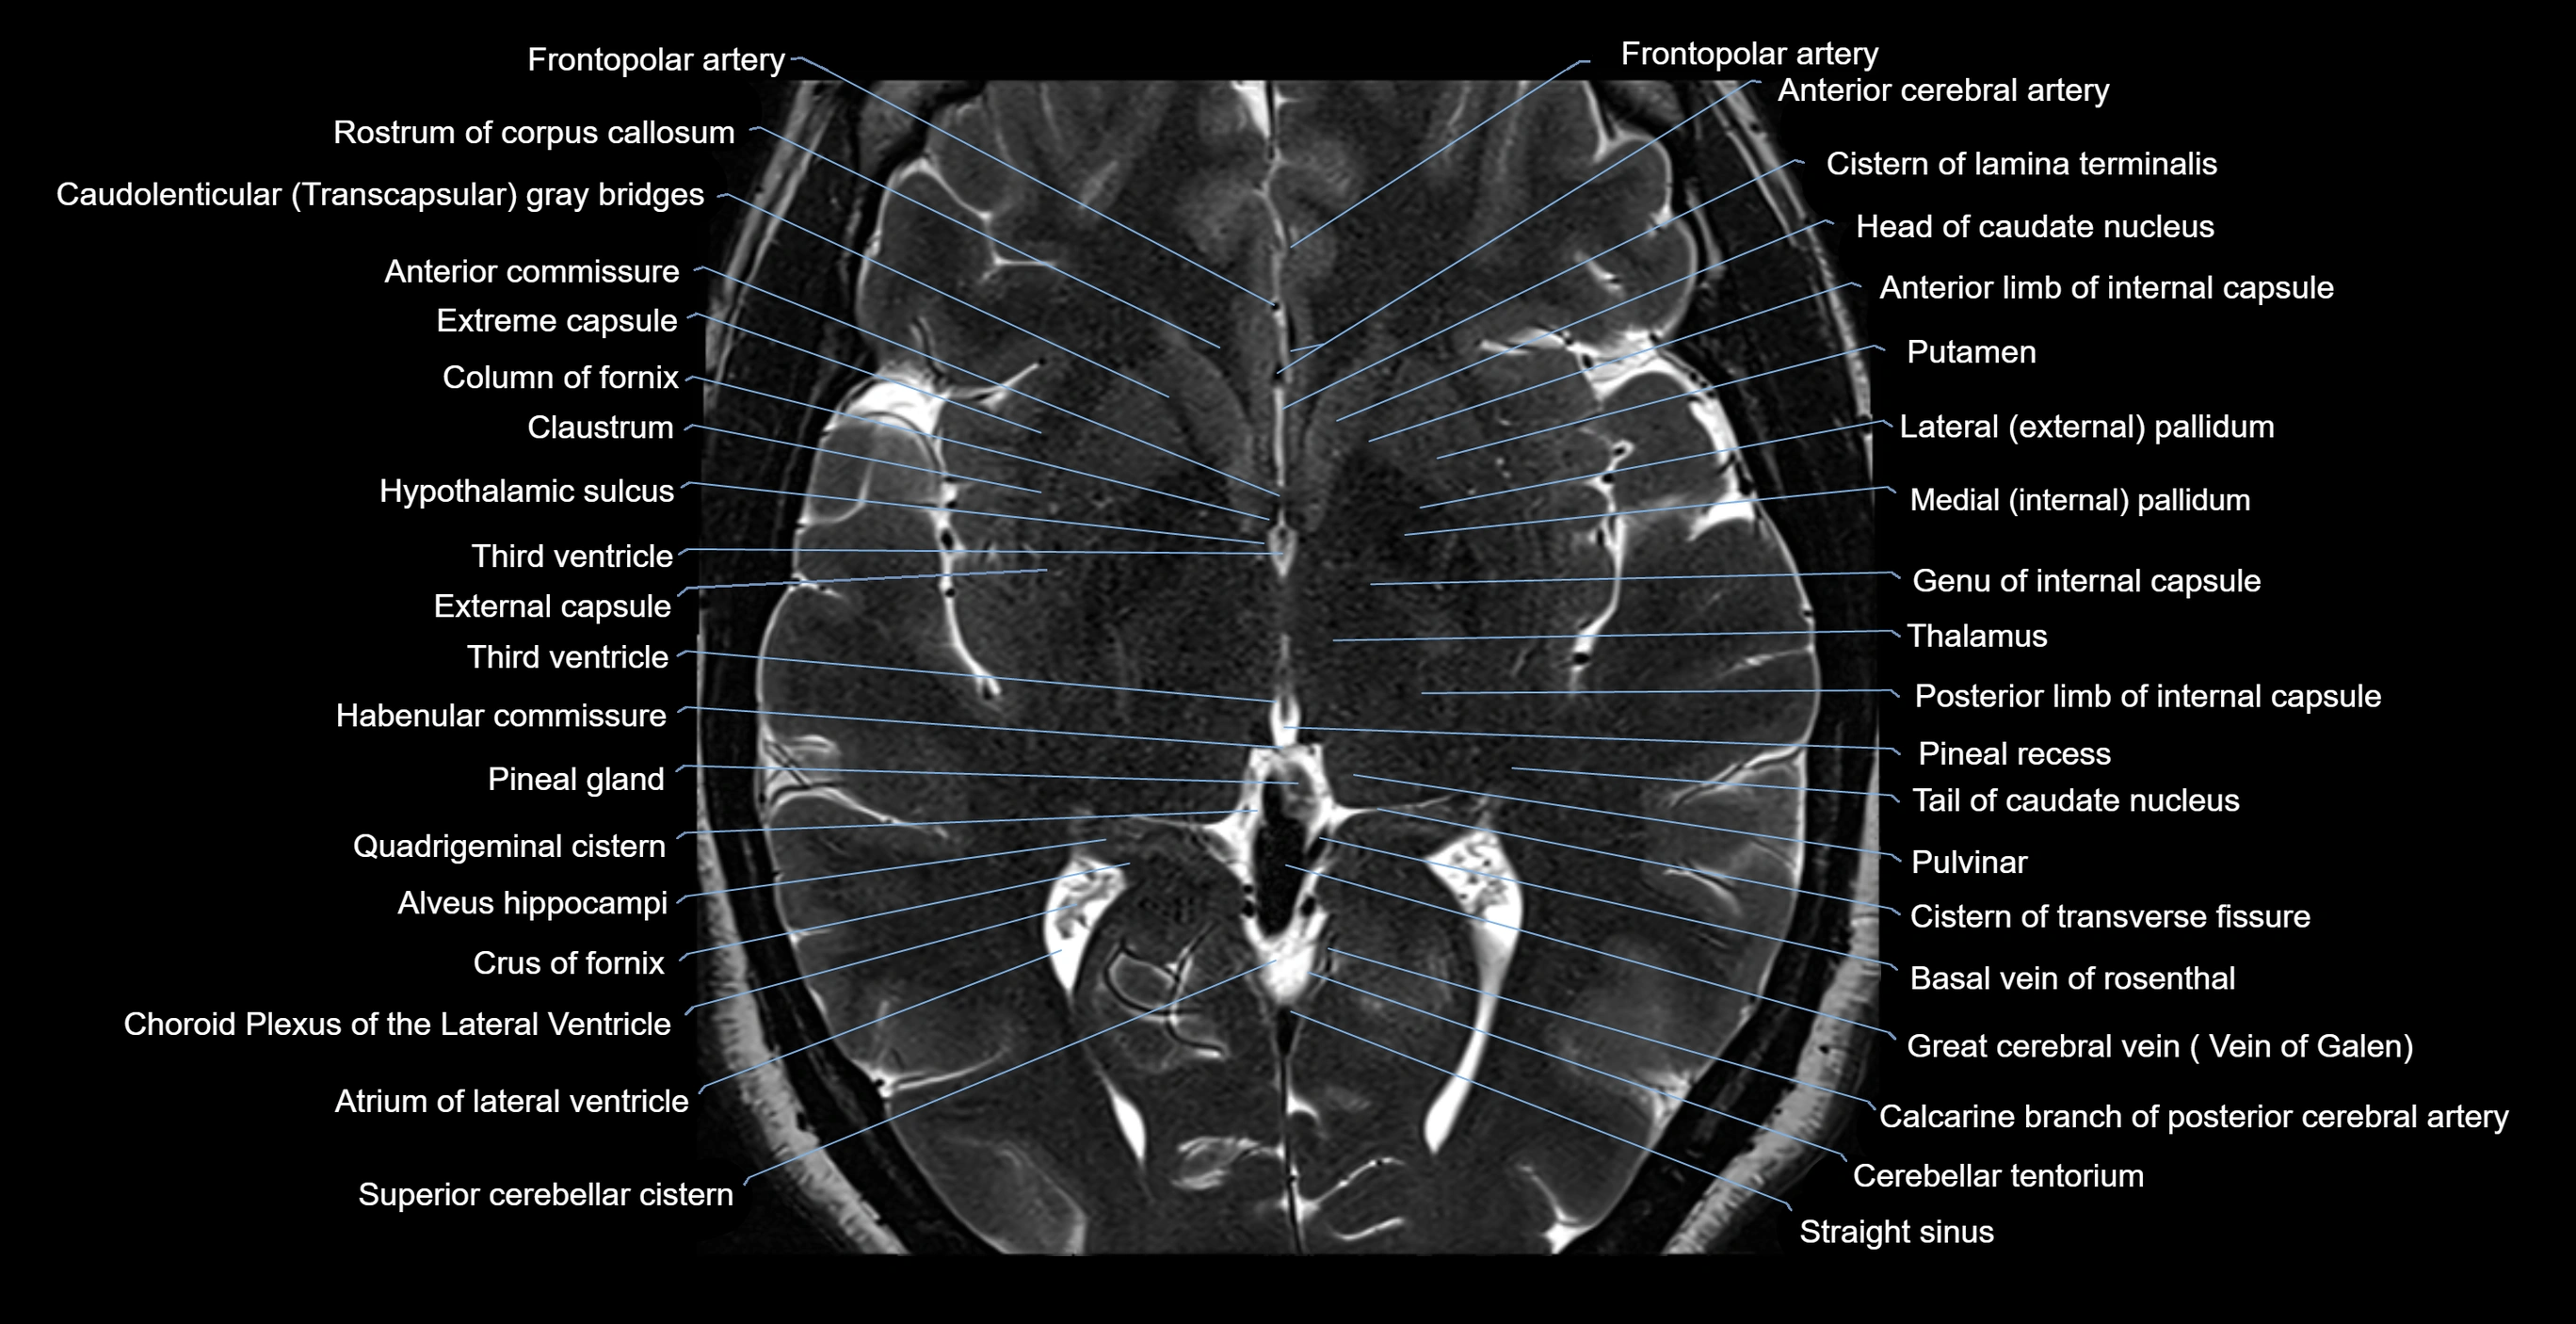

- Anterior commissure

- Anterior limb of internal capsule

- Basal vein of rosenthal

- Calcarine branch of posterior cerebral artery

- Cerebellar tentorium

- Choroid plexus of the lateral ventricle

- Cistern of lamina terminalis

- Cistern of transverse fissure

- Claustrum

- Column of fornix

- Crus of fornix

- External capsule

- Extreme capsule

- Frontopolar artery

- Great cerebral vein

- Habenular commissure

- Head of caudate nucleus

- Hypothalamic sulcus

- Inferior sagittal sinus

- Internal cerebral vein

- Lateral pallidum

- Medial pallidum

- Pineal gland

- Pineal recess

- Posterior cerebral artery

- Posterior limb of internal capsule

- Pulvinar

- Putamen

- Quadrigeminal cistern

- Rostrum of corpus callosum

- Straight sinus

- Superior cerebellar cistern

- Tail of caudate nucleus

- Tenia of fornix

- Thalamus

- Third ventricle